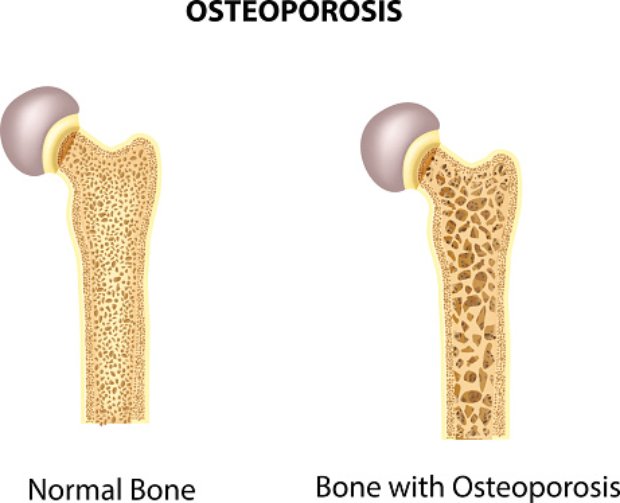

If you’re over the age of 50, then bone health is a serious concern—even more so if you’re a woman. When a person develops osteoporosis, their bones become weak and brittle, which increases the risk of fractures. Osteoporosis also negatively impacts mobility and can lead to isolation and depression. Osteoporosis is often called “the silent ...click here to read more